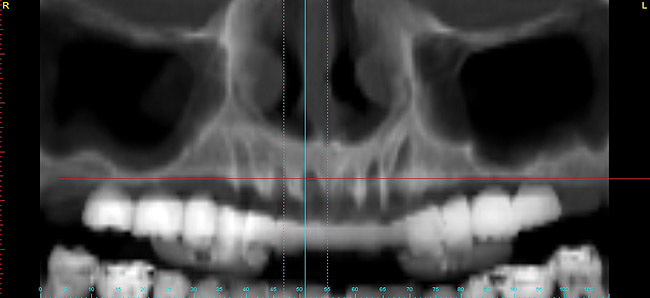

Figure 19   Panographic view 6 months post-graft showing substantial bone regeneration.

Figure 19

After 6 months of healing, a CBCT scan was taken and good bone formation was seen on the axial (Figure 18) and panograph (Figure 19) views. The CBCT was then used to plan for placement of dental implants (Figure 20). Upon full-thickness reflection of the ridge, abundant bone contour was observed. Internal hex dental implants (BioHorizons) were placed according to the locations planned on the CBCT (Figure 21). After a healing period of 4 months, the implants were uncovered (Figure 22) and abutments were placed (Figure 23). A panograph taken 1 year after this stage revealed the final restorations on well-integrated implants (Figure 24). The patient’s smile reveals a fixed prosthesis that simulates her natural teeth (Figure 25).